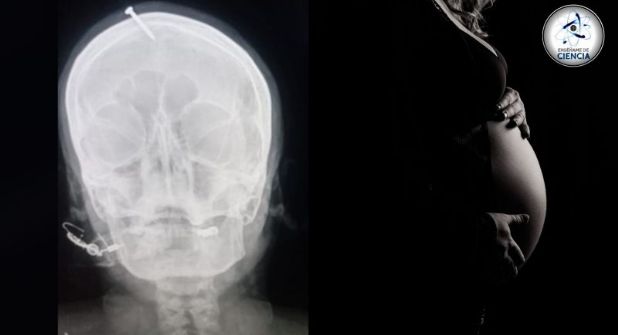

Fue así como el pseudo experto comenzó a introducir un clavo por la cabeza de su paciente, llegando poco a poco hasta adentro de su cabeza. Luego de sufrir intensos dolores, la implicada acudió al centro médico de Peshawar para retirar el objeto metálico, del cual había fallado para quitar de su sistema.

Tras examinar a la mujer embarazada se determinó, gracias a un escáner, el lugar el clavo del curandero, el cual fue enterrado en el cráneo sin llegar afortunadamente al cerebro.